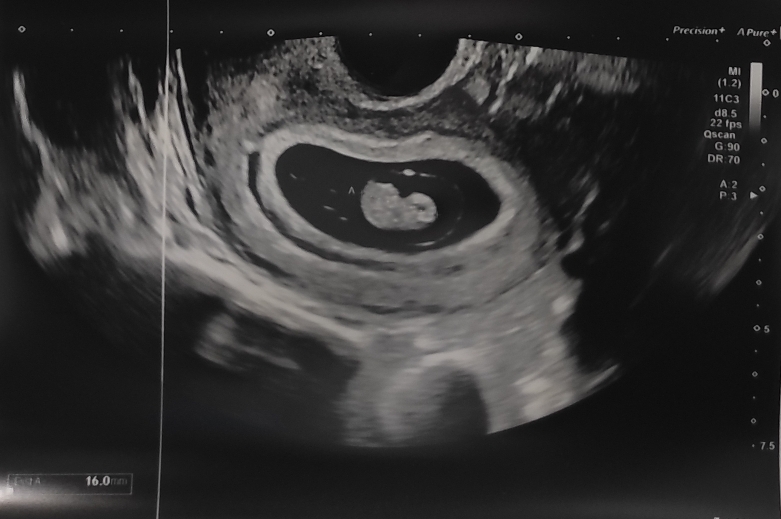

- La Noticia

Ya habían pasado dos semanas y en la primera prueba… Lee más: La Noticia